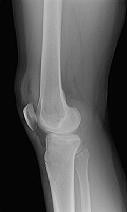

Figures 1 and 2 are the radiographs of a 35-year-old man who is brought into the emergency department after a motor vehicle collision. He is complaining of isolated knee pain. Examination reveals swelling, blood filled blisters, popliteal ecchymosis, joint line pain, and limited knee joint motion. His pulses and sensation are normal.

**CLINICAL SITUATION**

Figures 3 through 8 are the axial and sagittal CT scan sections of the injury. Intra-operative patient positioning for definitive fixation should be

The surgical approach for definitive reduction and stabilization of this pattern is